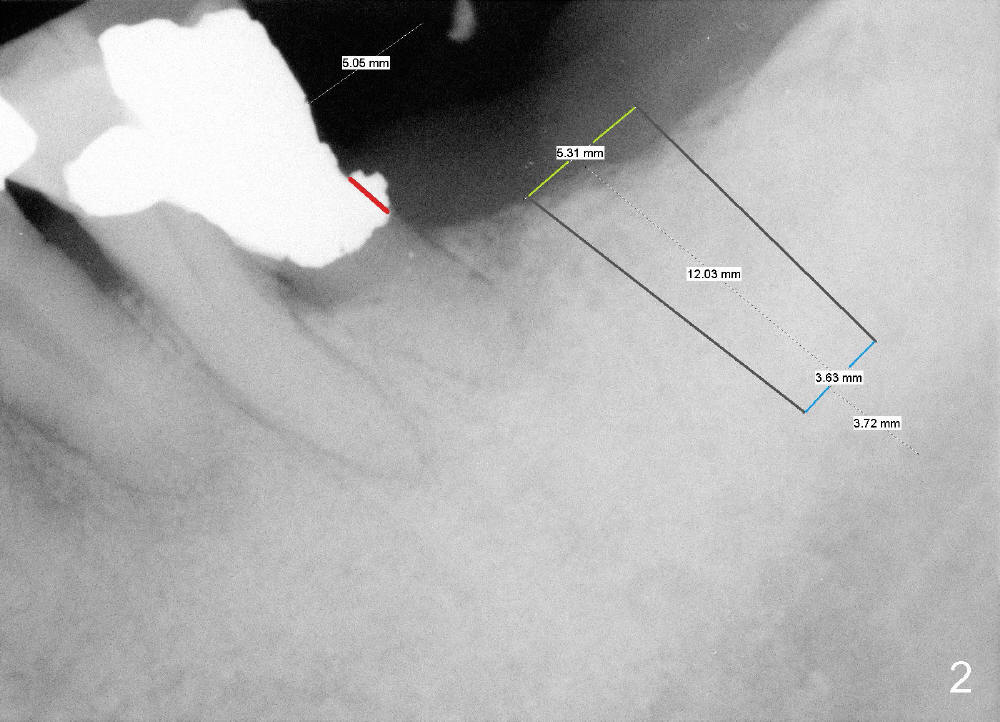

After local anesthesia, amalgam overhang (*) in the distal cervical area of the #19 is examined.  If it is subgingival, a small incision is made to expose and trim it (Fig.2 red line). If it is easily removed without incision, a 4 mm tissue punch is used for #18 osteotomy.  For safety, a submerged implant system will be chosen for this case, since the surgical kit has drill stoppers.  The first intraop PA will be taken following 2 mm pilot drill at 8-10 mm deep.  A 5.3x12 mm implant is expected (Fig.2)